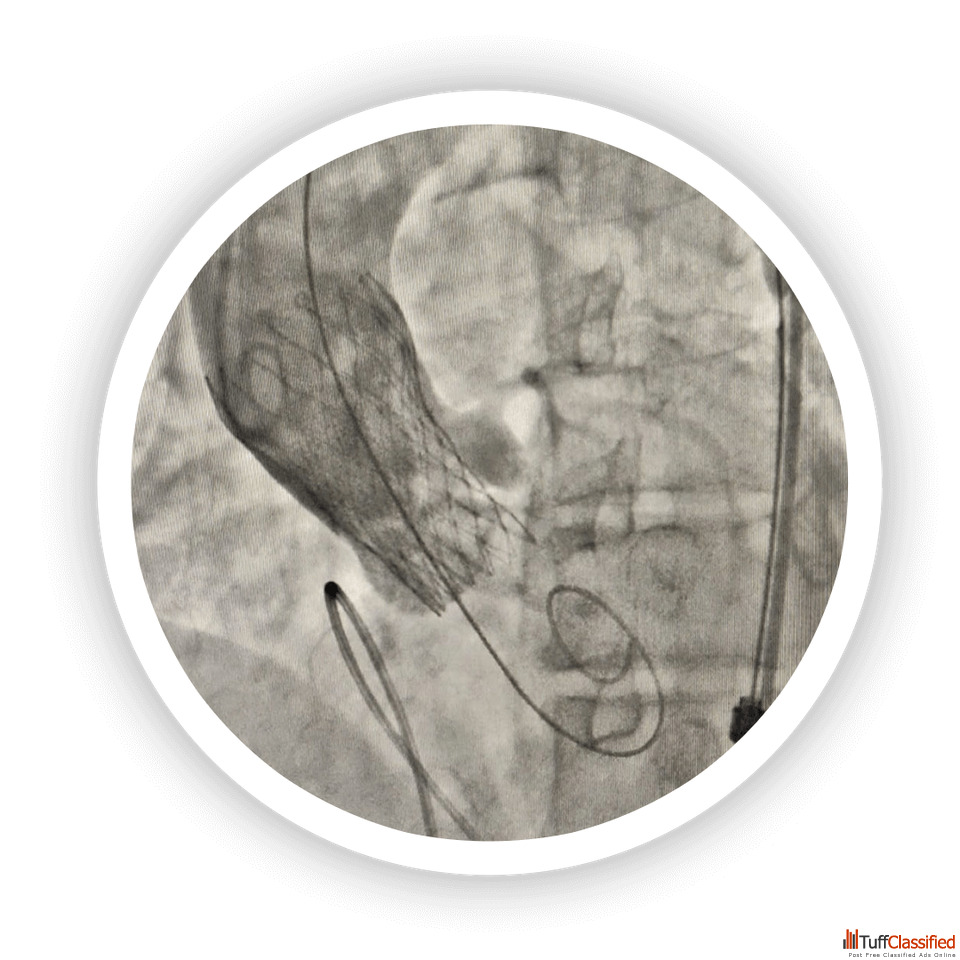

Patients diagnosed with severe mitral valve narrowing may benefit from the bmv Procedure, a minimally invasive alternative to traditional surgery. The bmv Procedure uses advanced imaging and catheter technology to open a stiff or narrowed valve, improving blood flow and reducing symptoms like shortness of breath and fatigue. It is particularly effective for younger patients with rheumatic heart disease. Recovery is typically quick, with most patients discharged within a few days. This procedure has significantly improved quality of life and reduced hospital readmissions for cardiac complications.